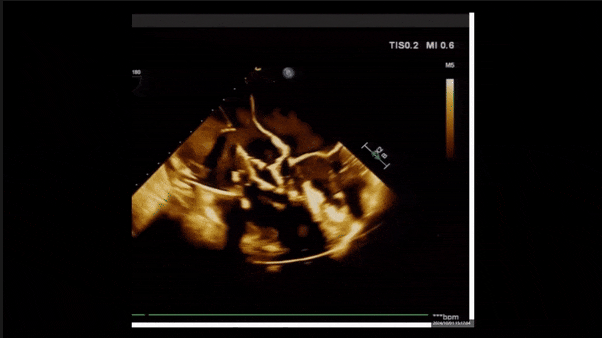

術后即刻返流

術后即刻返流三維

術后三維超聲

術后即刻經食道超聲可見,三尖瓣假體瓣膜位置合適,牛心包瓣葉運動狀態良好,開閉正常,瓣周及瓣葉對合緣處未見明顯返流,心電圖及心包狀態較術前無明顯變化。

術前術后返流情況對比